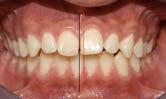

Figura 2. Imagen representativa de una luxación extrusiva en el órgano dental 11 que presenta un cambio de coloración en la encía.

necrosis pulpar. Las lesiones por luxación extrusiva requieren un tratamiento inmediato, consistente en reposicionamiento y estabilización. El tratamiento comienza con un correcto diagnóstico clínico y radiográfico, seguido del reposicionamiento manual del diente en el alvéolo y la colocación de una férula flexible, para permanecer in situ durante aproximadamente 2 semanas.6

Entre todas las lesiones orofaciales, las lesiones dentales traumáticas (TDI) son una de las más prevalentes. Representa el 18% de todas las lesiones en niños de 0 a 6 años (Figura 2) y Las lesiones por luxación se pueden clasificar en varios tipos según el grado de desplazamiento: conmoción cerebral, subluxación, luxación lateral, extrusión y avulsión. La raíz del germen del diente temporal y del permanente se encuentran muy cerca, por lo que las complicaciones a largo plazo de las TDL, como la infección de los dientes temporales, también pueden dañar los dientes sucesores en desarrollo. La prevalencia de lesiones por luxación es alta entre los niños pequeños debido a la naturaleza resistente de su hueso alveolar y sus estructuras de soporte (Figura 3). Se ha informado que las lesiones por intrusión causan más alteraciones de la mineralización en